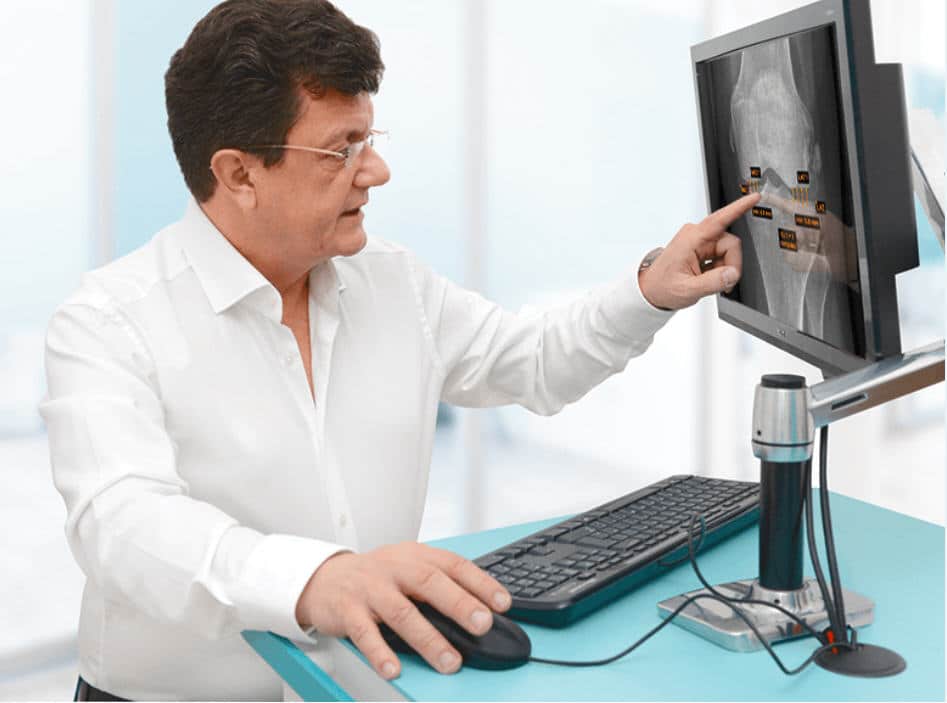

Dr. Richard Ljuhar: Targeted treatment options ensure shorter periods of suffering, quicker recovery by applying objective assessment/progression measurements and prevention/delay of disease progression, leading to better outcomes. Enhanced and well-structured reports ensure ideal patient communication. MSK diagnoses are often time-consuming and subjective. IB Lab supports radiologists and orthopedists in their daily decision-making with standardized, fast and resource-effective AI-based software solutions for automated measurements on radiographs that accelerate the workflow and improve the time and quality of patient care.

IB Lab applications can save up to three minutes of interpretation time per X-ray, saving up to 45 to 60 extra minutes per day for a radiologist.